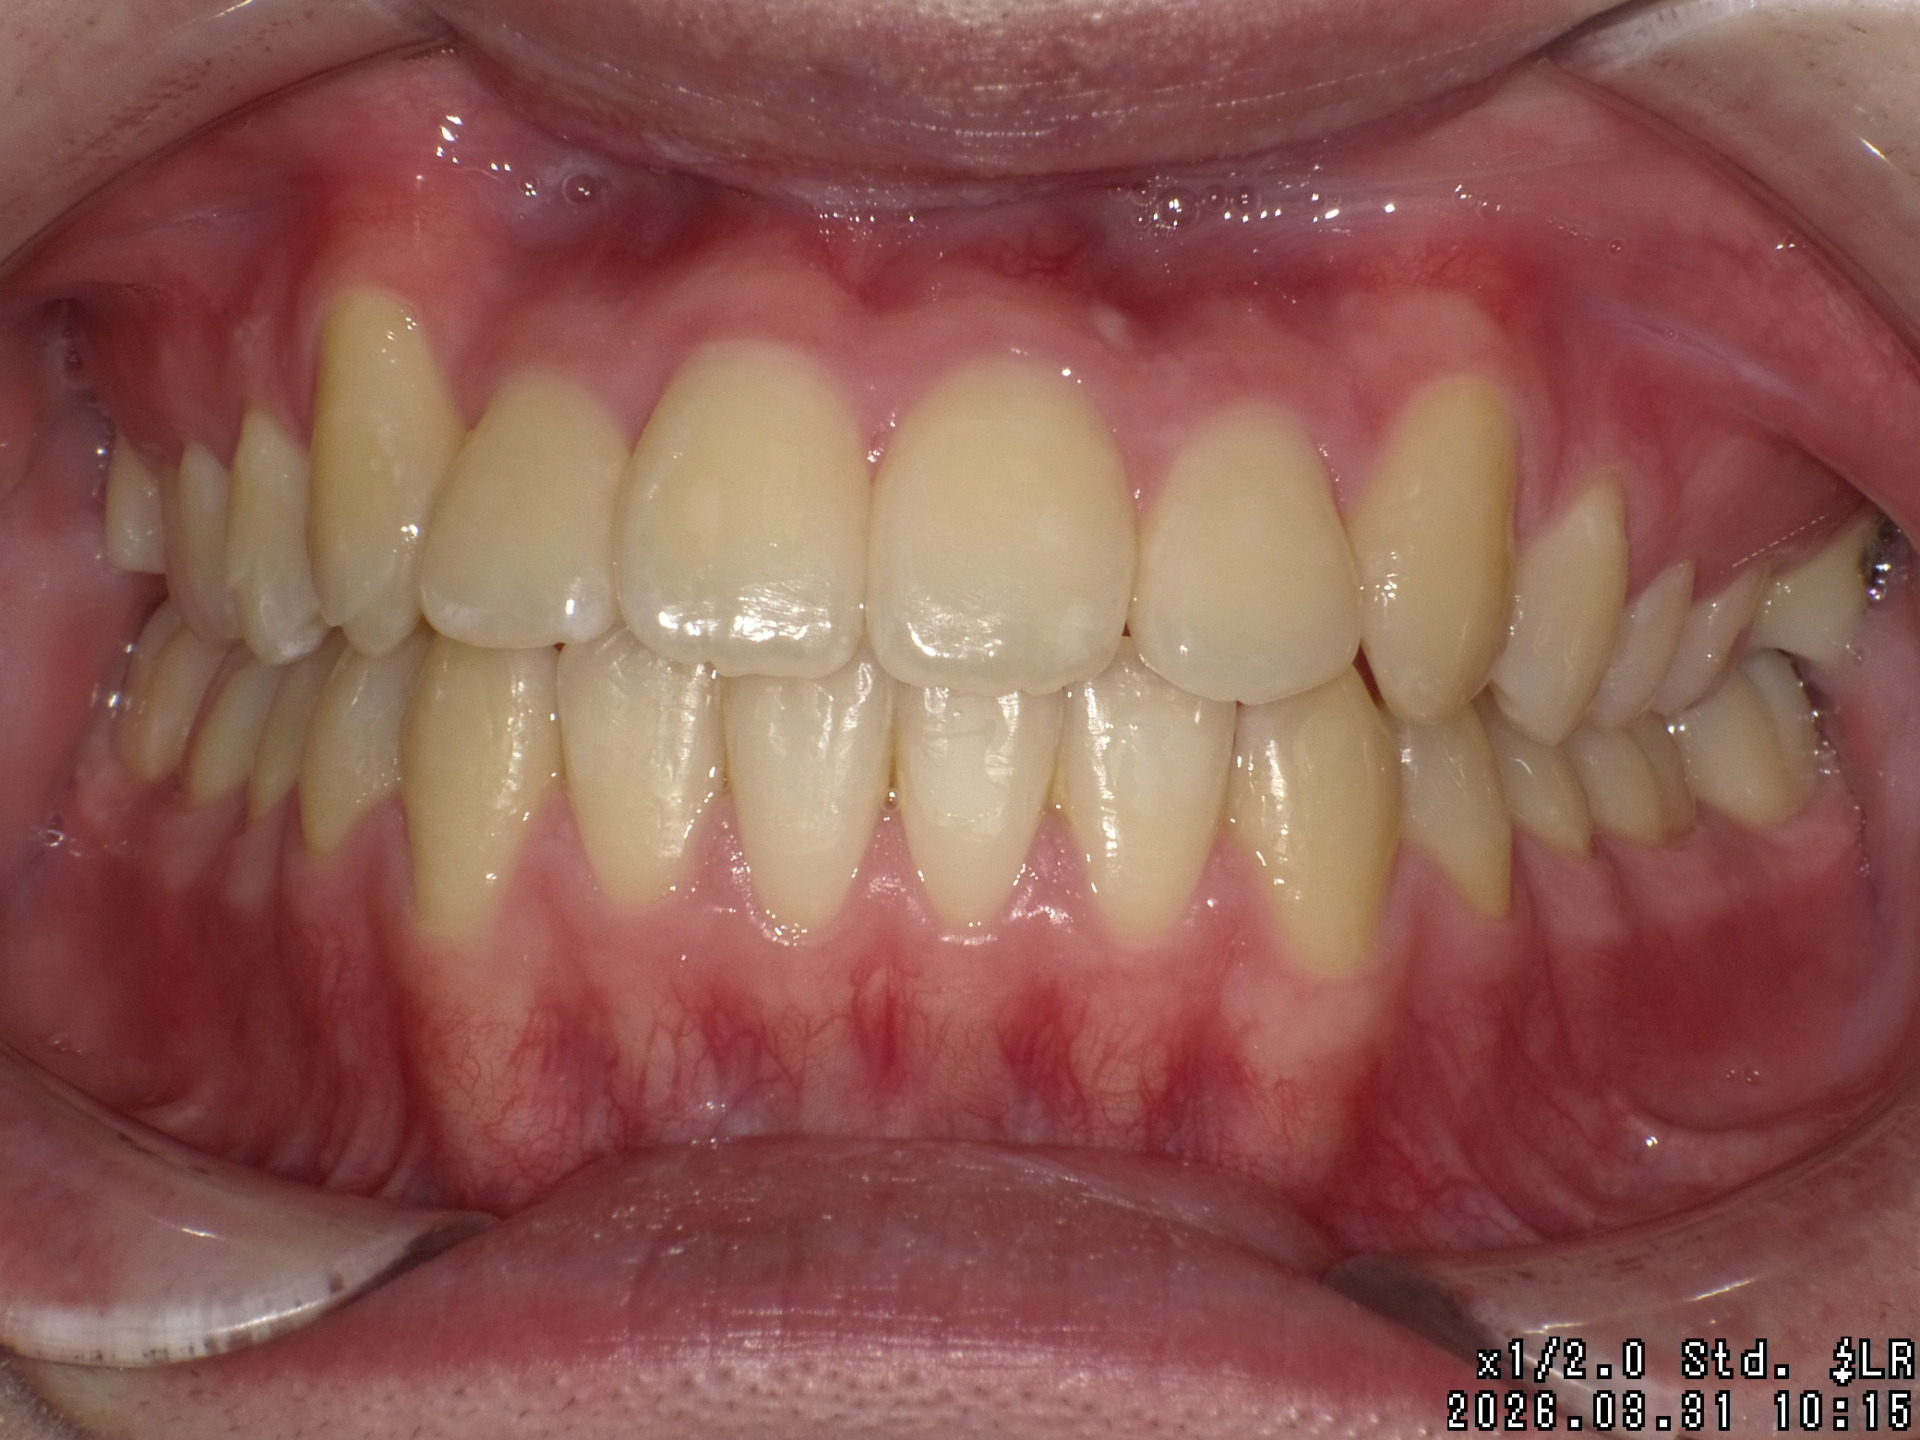

After